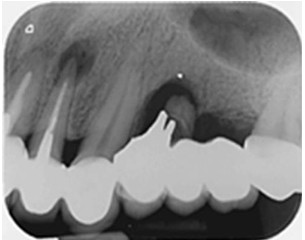

缺牙問題在牙科治療上有多種選擇方式。傳統的重建咬合功能方式是將缺牙區相鄰的牙齒磨小並作為支柱,使前後牙齒相連,稱作牙橋。

由於牙橋製作需磨損結構完好的自然牙,且日後牙橋清潔不易,而有可能導致牙周病、二次蛀牙的發生率較高,現今社會大眾對於缺牙時以人工植牙方式重建咬合功能的接受度已越來越高。

植牙技術尚未發展成熟前,面臨缺牙問題時,需將缺牙處前後相鄰的牙摩小作為支柱,以兩顆牙背三顆牙的方式連在一起,稱作牙橋。

牙橋牙冠相連,導致近牙齦處的牙縫清潔不易,因而容易產生牙周病問題。又因為一次需要製作多顆假牙,多數人選擇趨向於價格低廉的假牙材質,劣質的金屬造成二次蛀牙的風險大增。一旦其中一顆牙發生狀況,整組牙橋就需要重新製作。